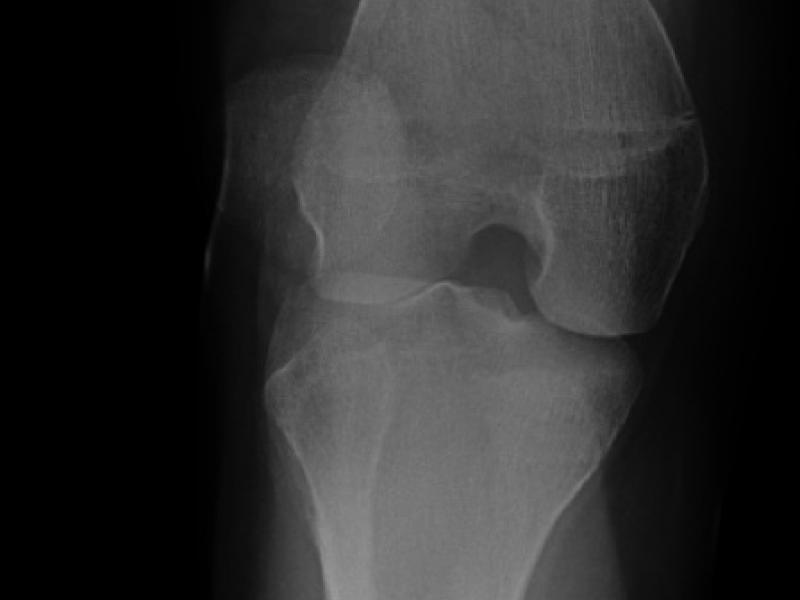

A 16 yo female presents with knee pain after her knee was

What's the diagnosis?  By Dr. Erica Schramm